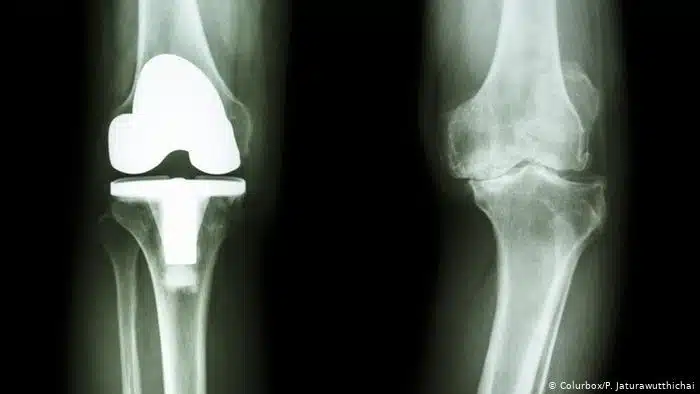

تعتبر عمليات الركبة كثيرة ومتعددة ولها الكثير من طرق العلاج التي يلجأ لها الطبيب حسب كل حالة ومدى تعقيدها، ومن هذه العمليات عملية تغيير مفصل الركبة وتعتبر هذه العملية صعبة وحساسة، ونوضح في هذا المقال أهم التعليمات التي تخص العملية وطريقتها والعديد من المعلومات المهمة فكونوا معنا.

- يقوم الطبيب بإجراء شق في الركبة للوصول إلى المفصل المتضرر، بعد ذلك يبدأ الطبيب في إزالة الأنسجة والأربطة المتضررة ثم يبدأ في استبدال المفصل التالف بآخر صناعي.

- بعد ذلك بقوم الطبيب في تثبيت المفصل الجديد.

ما هي أنواع مفصل الركبة الصناعي ؟

هناك عدد من أنواع مفاصل الركبة الصناعية، وذلك لتتناسب مع الأشخاص، ومن هذه الأنواع ما يلي:

- مفصل معدن على بلاستيك: يعتبر هذا النوع من المفاصل الأقل سعر في الفئة الخاصة به كما أنه يعيش مدة طويلة ولكن مشكلته الوحيدة أن بعض الأجسام لا تستجيب معه.

- مفصل سيراميك على بلاستيك: يلجأ له الأطباء في العادة عند يكون المريض متحسس من المعدن.

- مفصل سيراميك على سيراميك: وعادة ما يكون مريح وسلس ولكن عيبه الوحيد أنه يصدر أصواتا عند المشي.

- معدن على معدن: يعتبر أقل أنواع المفاصل استخداما وهذا للمخاوف من تسرب المعدن داخل الجسم مما قد يؤثر بالسلب على باقي الأنسجة.